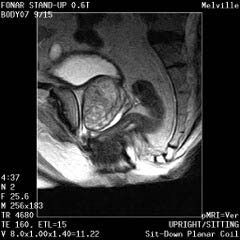

The Prostate without an Endorectal Probe |

The Heart |

![]() |

| Prostate: Delineation of Peripheral Zones (PZ), Cortical Zone (CZ) and Vescicles without an Endorectal Coil. | |

Cervical Spine |

|

Upright Neutral |

Upright Extension |

Unsuspected

Disc Herniation in Extension |

The Liver, Kidney

and Small Intestine

Bladder

and Uterus in Pelvic Floor Dysfunction (PFD) |

Lumbar Spine |

Recumbent, Weightless |

Upright, Weight-Bearing |

Figure 8.

Figure 8a-8d.

Further examples of the exceptional anatomic detail

made visible by the DISCOVERY

of Damadian of the pronounced differences in the decay

rates (relaxations) of the NMR signals

of the body's normal tissues (Figure

6). The DISCOVERED

differences supply the pixel amplitude differences

"PIXEL CONTRAST (IMAGE DETAIL)"

that produce, for the first time in medical history,

the detailed visualization of normal human anatomy

MRI is noted for. Note the visualization of the

vestibular and cochlear nerves

WITHIN

the internal auditory canel (Figure 8b) and the visualization

of the hypothalamic

tract (that transports hormones from

the brain) WITHIN

the pituitary stalk. (Figure 8c)